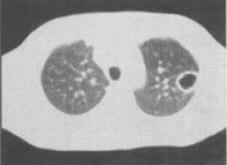

患者女,49岁,午后低热,咳嗽2个月余,结合影像学检查,最可能的诊断是()。

A、肺癌

B、肺结核

C、肺脓肿

D、肺囊肿

E、支气管扩张

B